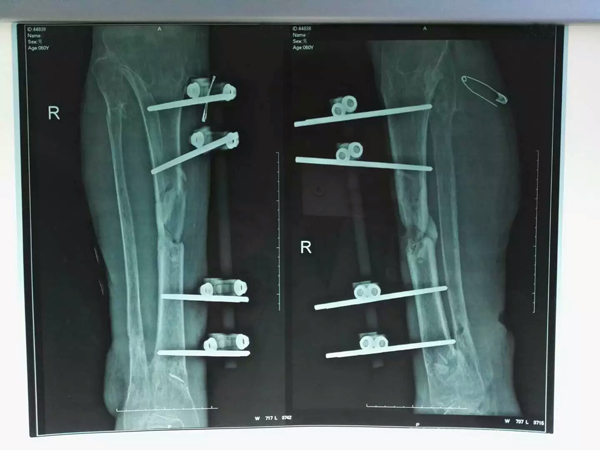

術(shù)前

患者高某某,男,56歲,2014年7月因車(chē)禍致使右脛腓骨開(kāi)放性、粉碎性骨折,當(dāng)時(shí)被送至我市某私立醫(yī)院進(jìn)行治療,還聘請(qǐng)專(zhuān)家進(jìn)行了復(fù)位鋼板內(nèi)固定術(shù),術(shù)后雖然經(jīng)過(guò)抗炎對(duì)癥及連續(xù)換藥治療等對(duì)癥處理,但拆線后仍有一長(zhǎng)約3cm的傷口不愈合,且存在骨外露現(xiàn)象,先后花費(fèi)共計(jì)15余萬(wàn)元也未能痊愈,后因經(jīng)濟(jì)原因不得不出院回家。

回家后,由于傷口不愈合,經(jīng)常會(huì)感染,患者不得不一次又一次地回到醫(yī)院接受治療。經(jīng)過(guò)多家醫(yī)院診治后,傷口均未見(jiàn)好轉(zhuǎn)。有些醫(yī)院醫(yī)生建議患者實(shí)施截肢手術(shù),以防病變。幾經(jīng)輾轉(zhuǎn),患者轉(zhuǎn)到了市中醫(yī)院,經(jīng)醫(yī)院門(mén)診體格檢查及影像資料顯示,患者被明確診斷為右脛骨外傷后骨髓炎伴傷口不愈合,治療此類(lèi)疾病目前最可靠的方法是在骨髓炎骨質(zhì)處進(jìn)行截骨,然后進(jìn)行動(dòng)外固定架骨質(zhì)延長(zhǎng),也就是“截骨延長(zhǎng)術(shù)”。在與家屬進(jìn)行充分溝通后,詳細(xì)說(shuō)明了此手術(shù)的時(shí)間較長(zhǎng),術(shù)后效果也不一定理想等不良效果后,患者家屬仍愿意嘗試,遂決定為患者實(shí)施該手術(shù)。